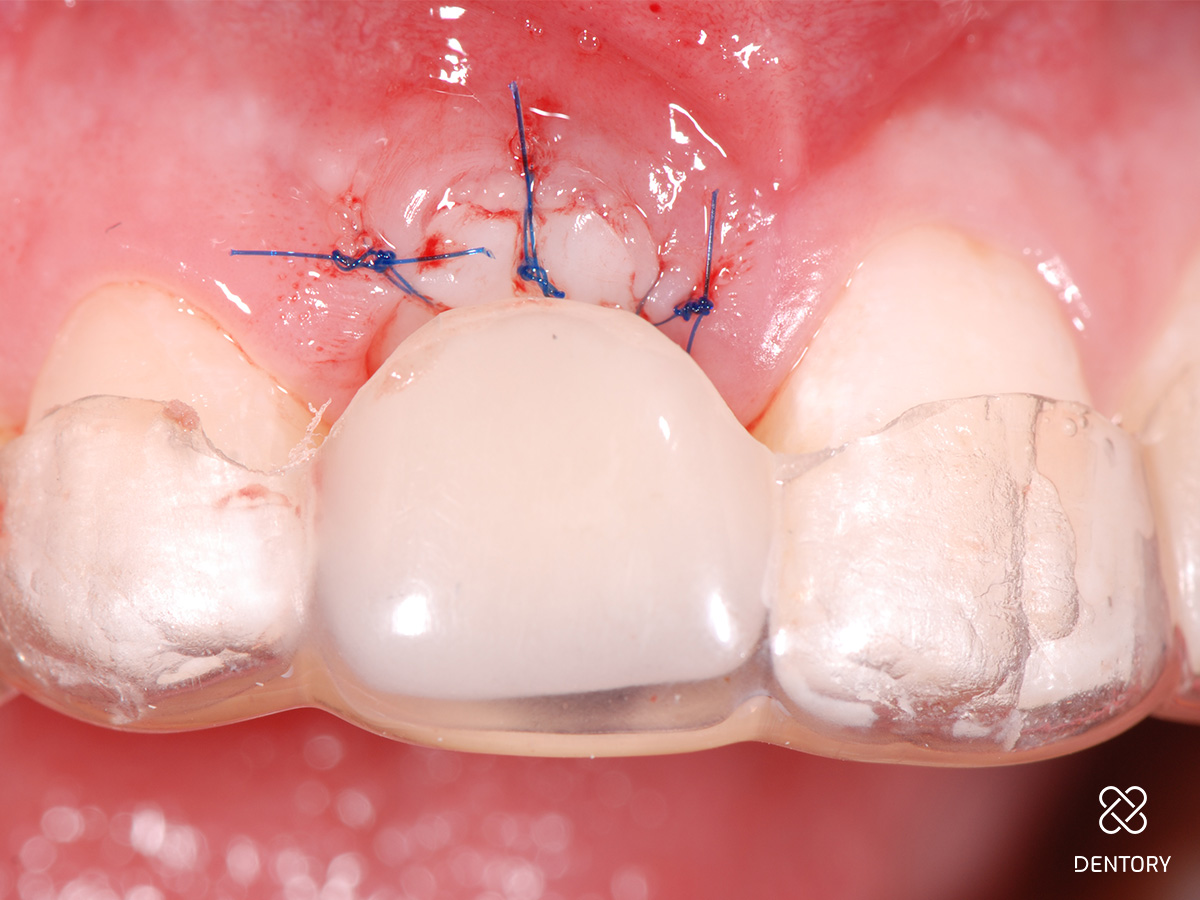

Abbildung 10

Eingenähter Punch vom seitlichen Gaumen: Die Entnahme kann im Prämolaren- oder Tuberbereich erfolgen.

Abbildung 11

Das Transplantat kann mit wenigen Mikronähten fixiert werden; die Passung sollte wie bei einem Korken mit etwas Druck sein.